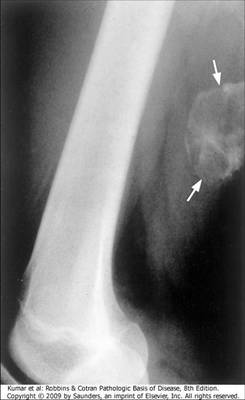

Dystrophic calcification occurs in dead/dying tissues in the absence of systemic hypercalcemia. Cell loses ability to regulate intracellular calcium and crystalline calcium phosphate forms.

Answer

• True

• False